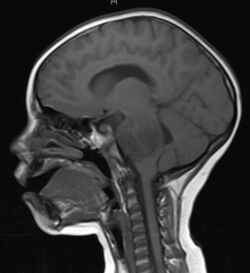

Diagnosis

A posterior fossa tumor leading to mass effect and midline shift

Although there is no specific or singular symptom or sign, the presence of a combination of symptoms and the lack of corresponding indications of other causes can be an indicator for investigation towards the possibility of a brain tumor. Brain tumors have similar characteristics and obstacles when it comes to diagnosis and therapy with tumors located elsewhere in the body. However, they create specific issues that follow closely to the properties of the organ they are in.[39]